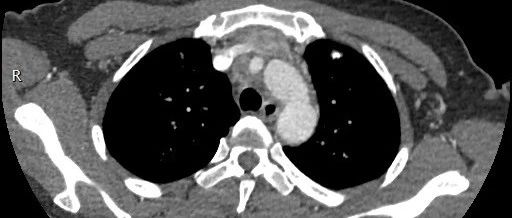

女性,间断胸痛3月,请诊断!

患者,女,58岁,接种流感疫苗后出现咳嗽、乏力和轻度发热就诊。进行短期抗生素治疗后,这些症状仍持续。

老年女性,间断胸痛3月,请诊断!